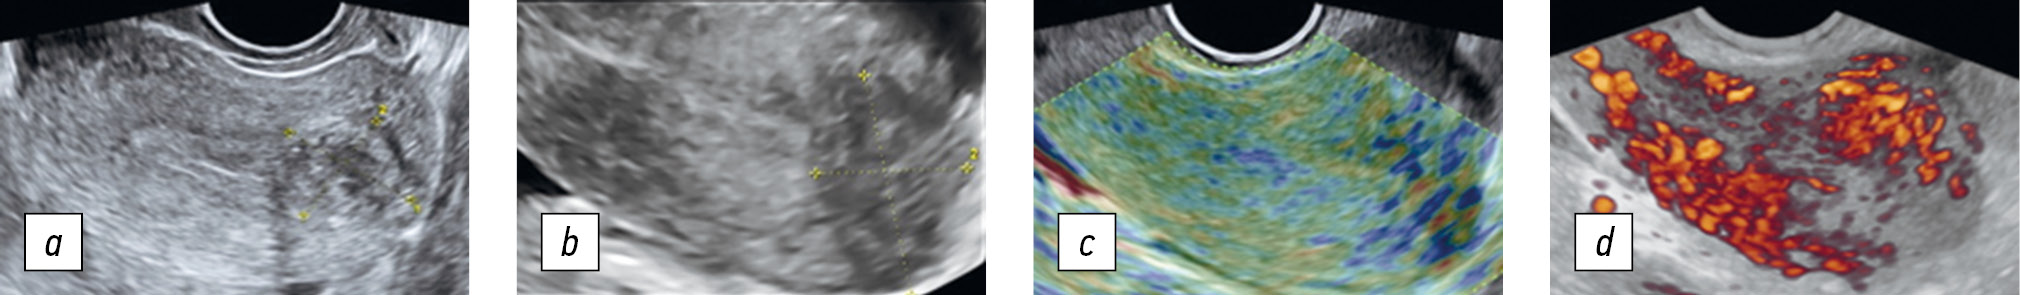

Рис. 6. Последовательное применение комплексной методики дифференциальной диагностики миомы матки и узла аденомиоза (диагностирована миома матки): а — в двухмерном режиме размер образования 23 × 18 мм; b — в трехмерном режиме размер образования 20 × 16 мм; c — по данным эластографии, коэффициент упругости 2,2; d — трехмерная реконструкция в режиме энергетического допплеровского кодирования с использованием методики glass body

Fig. 6. Consistent application of the complex technique for the differential diagnosis of uterine fibroids and adenomyosis node (uterine fibroid): a, 2D mode, the formation size is 23 × 18 mm; b, 3D mode, the formation size is 20 × 16 mm; c, elastography, strain ratio 2.2; d, 3D power Doppler glass body